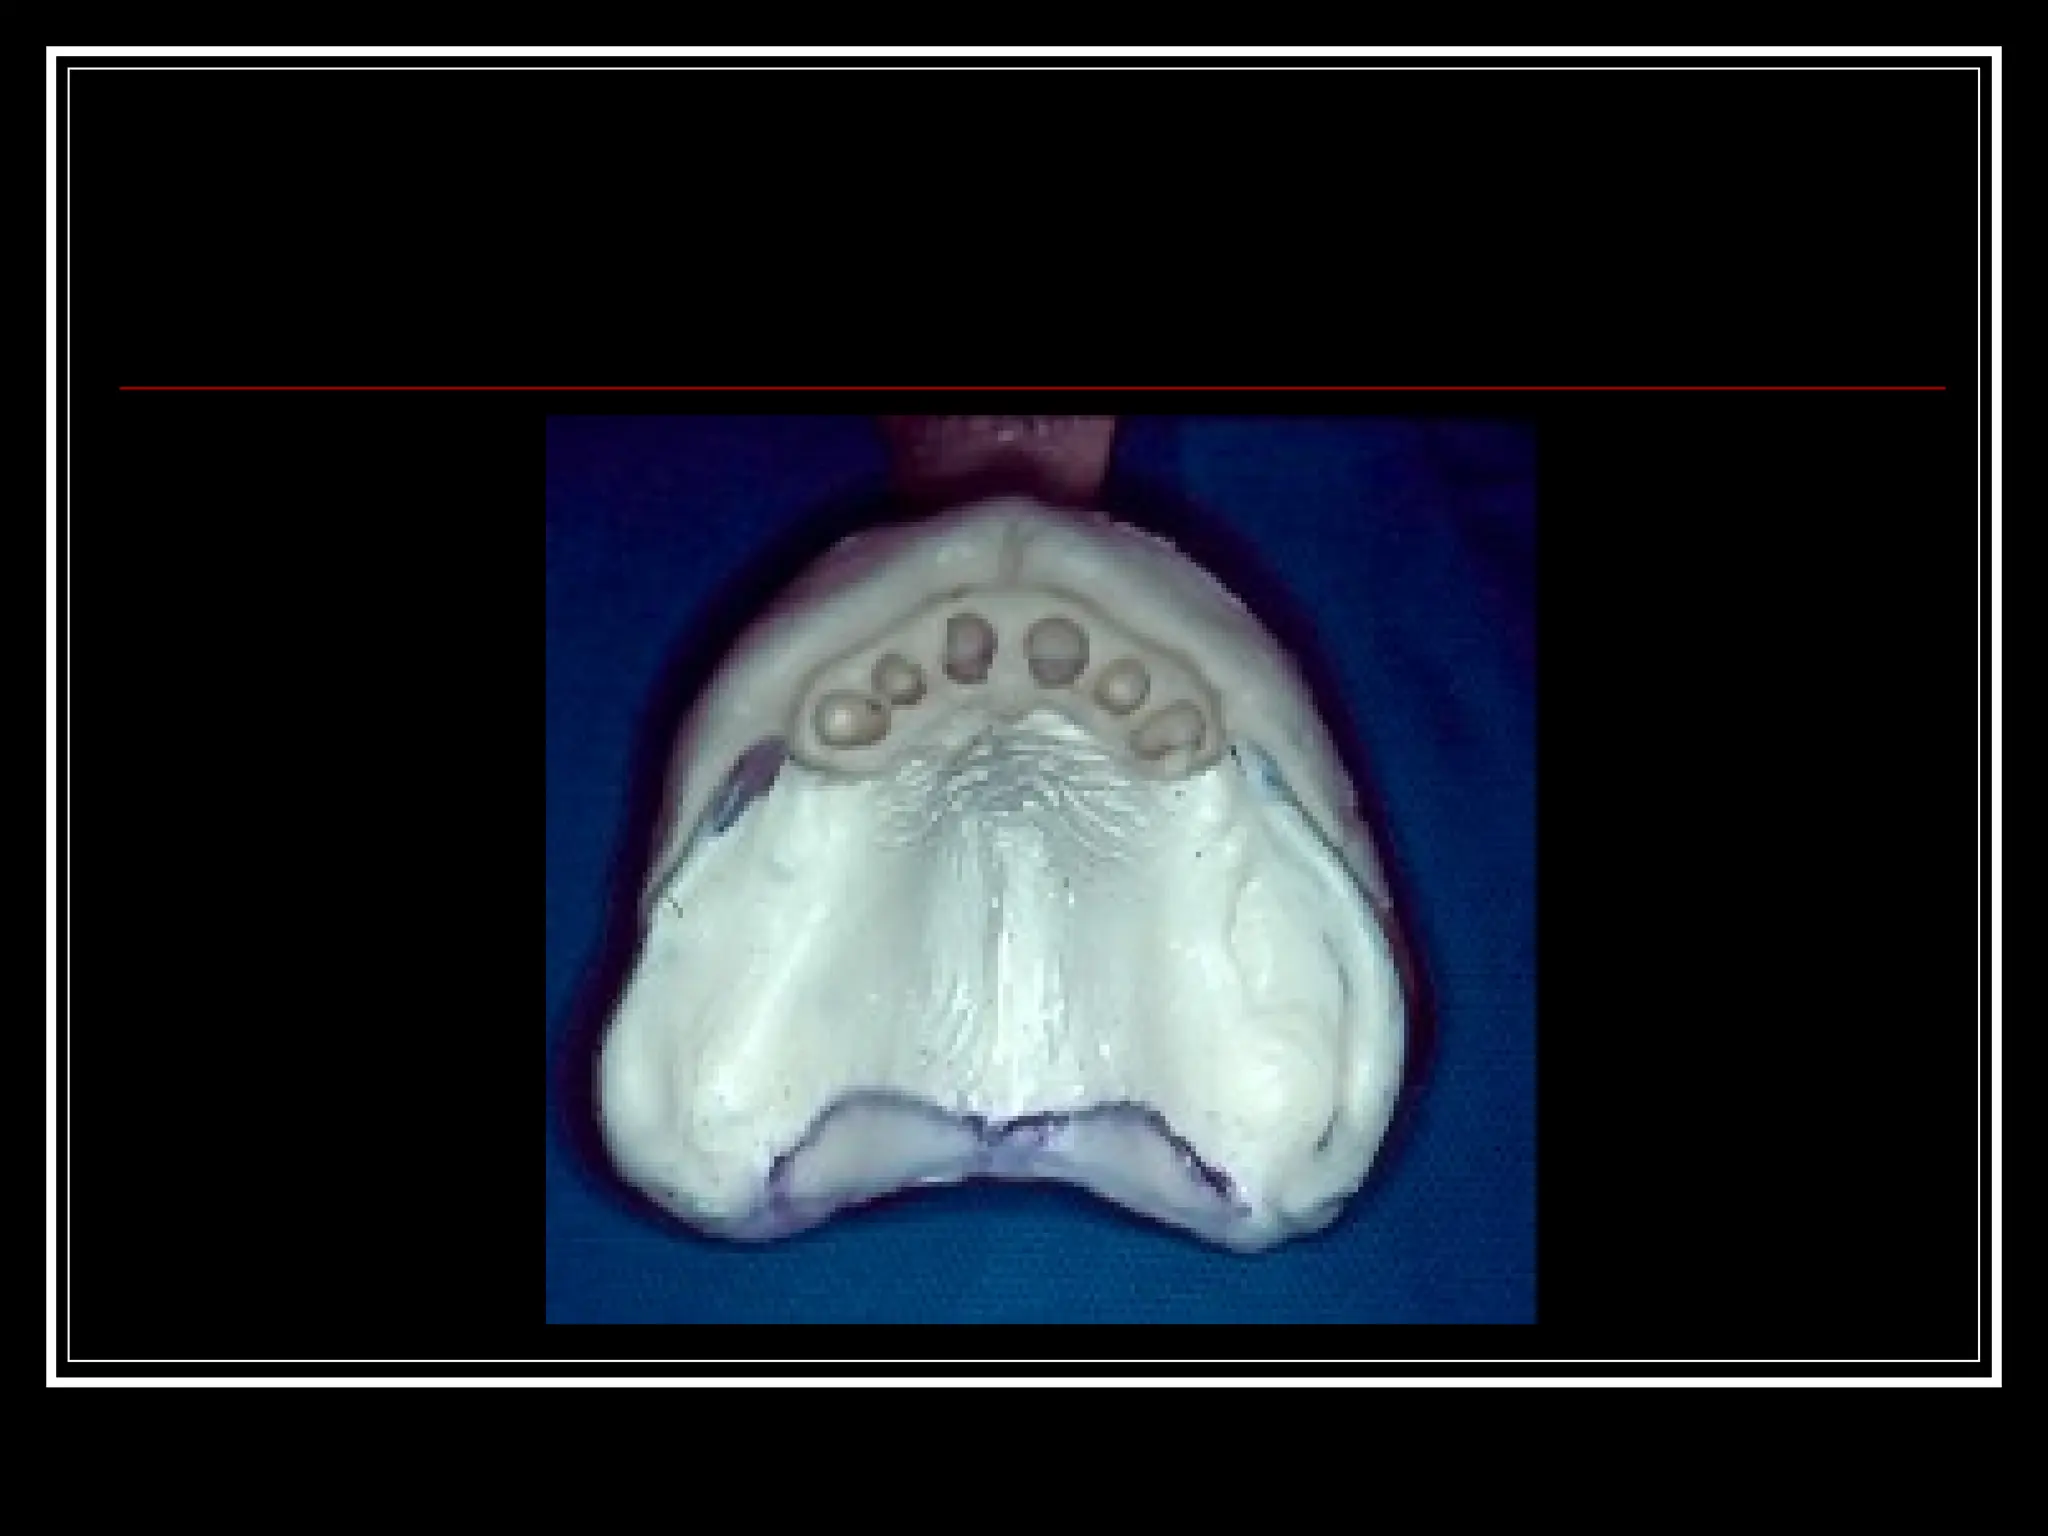

Majid B etal (2004)  Described fabrication of a clear surgical template that minimizes pressure caused by immediate complete dentures on a surgical area.